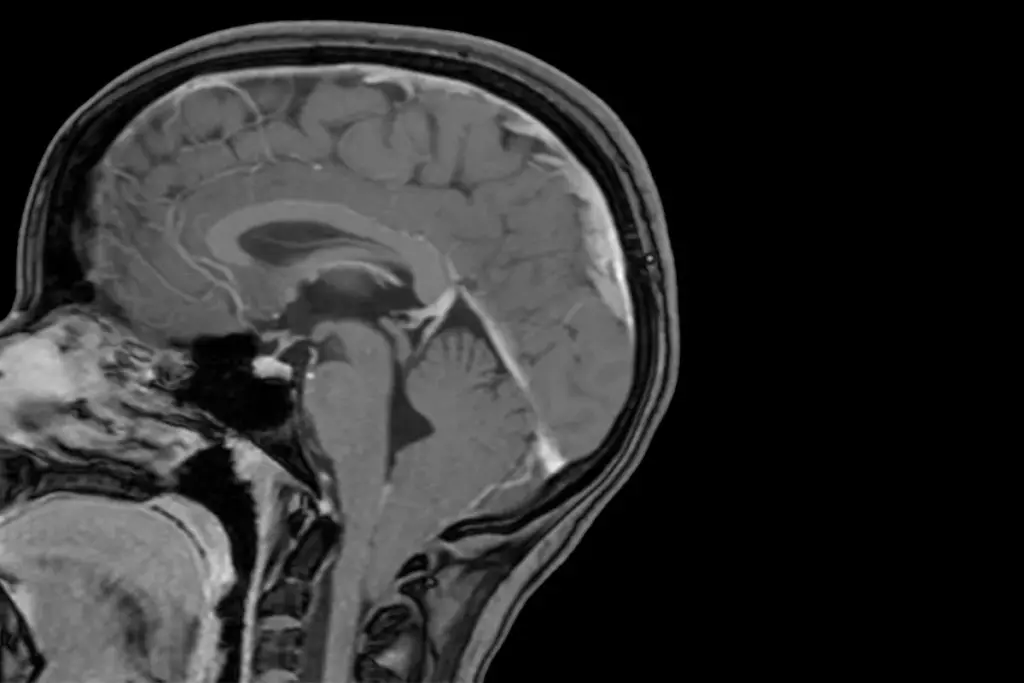

Imaging Techniques

Magnetic Resonance Imaging (MRI) is key for diagnosing Chiari malformation. It shows the brain and spinal cord in detail. Doctors can see the brain’s shape and any problems like syringomyelia.

At times, a Computed Tomography (CT) scan is used, mainly in emergencies. But CT scans are not as good as MRI for soft tissue issues. So, MRI is the top choice for Chiari malformation diagnosis.